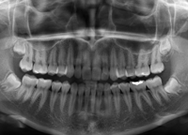

Radiografia Panorâmica

É uma radiografia de fácil obtenção, utilizada como exame inicial e complementar de diagnóstico por todas as especialidades da odontologia, pois permite a visualização dos dentes e das estruturas ósseas dos maxilares em uma única incidência.